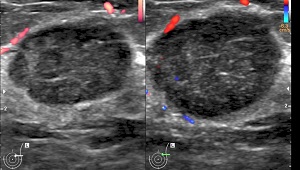

• Findings: Well defined, well encapsulated solid mass with well defined, sharp,lobulated margins.It may show calcification & cavitation.Quantative elastogram helps to diagnosis hardness of mass. Malignant mass lesions are harder than benign lesions. Ultrasould also diagnose their numbers, position, vascularity & degenerative changes, Fibroadenoma larger than 5 cms are known as giant fibroadenoma. Development of malignant changes in fibroadenoma are very rare however giant fibroadenoma may undergo malignant transfomation.